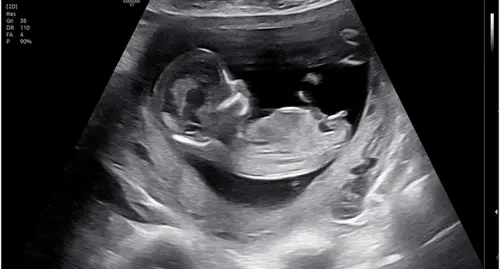

Boy or girl?

Wat denken jullie bij deze hahah

Girl denk ik